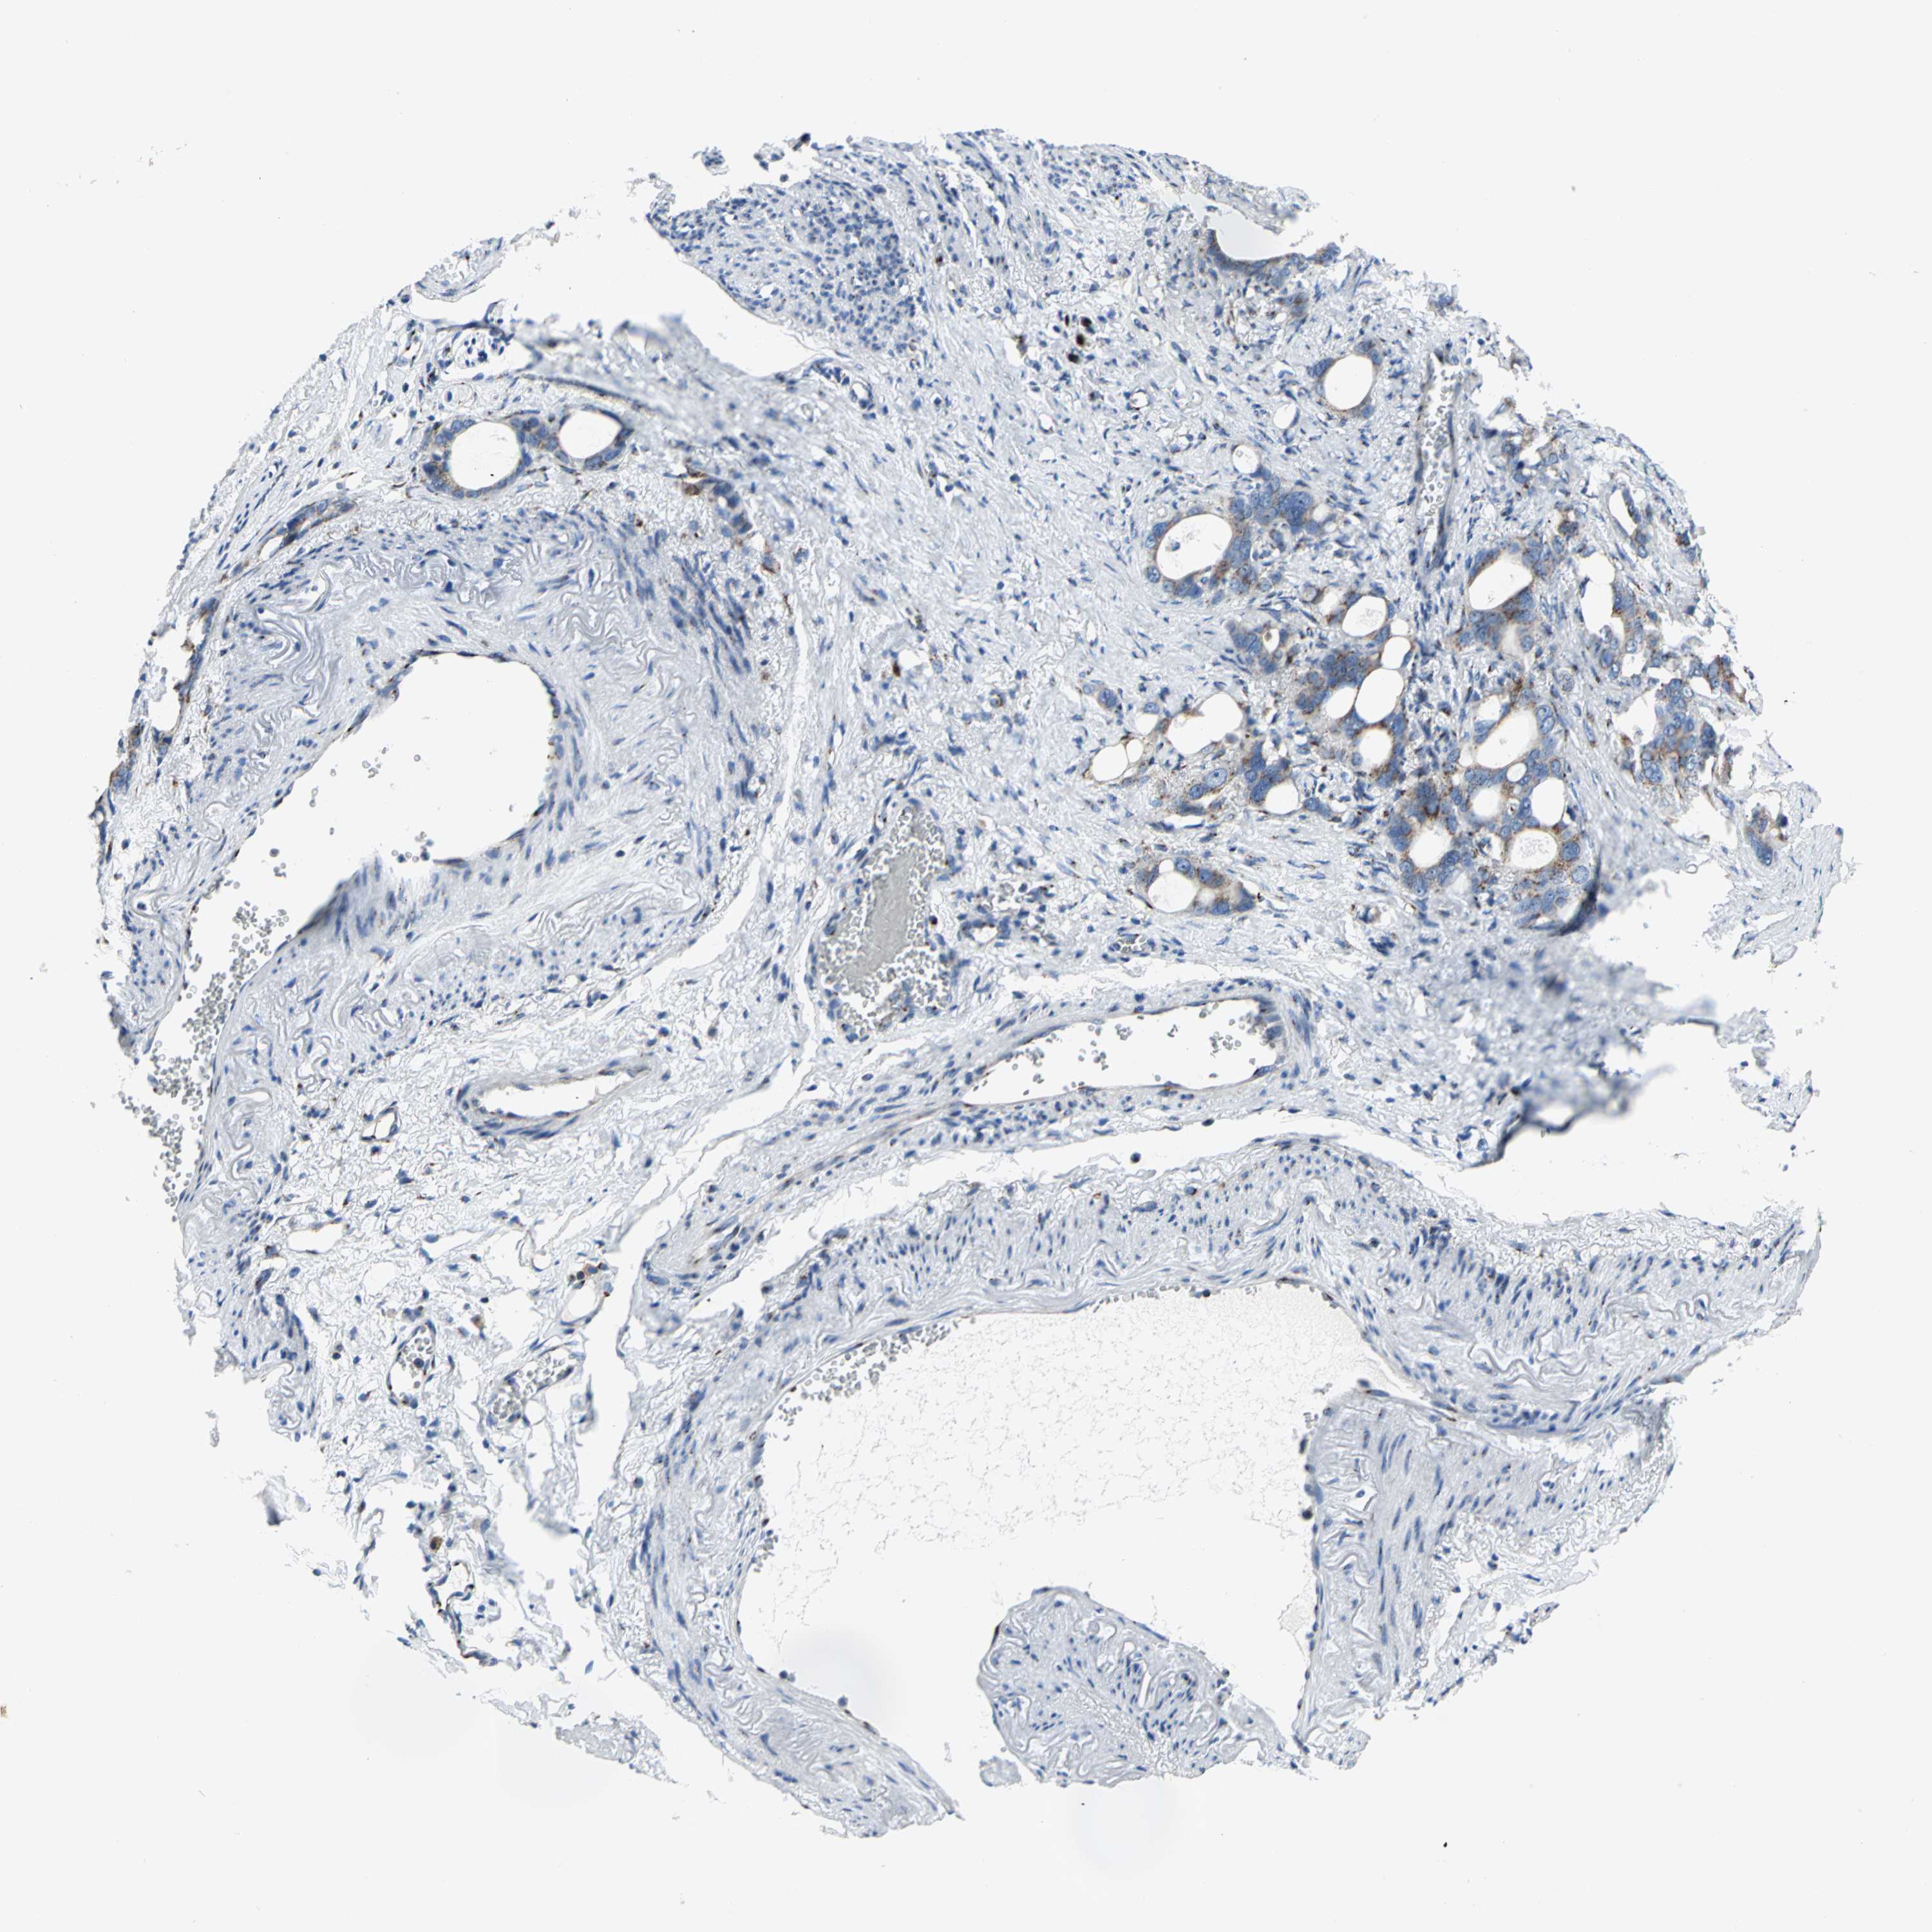

STOMACH CANCER - Protein expressioni

A mouse-over function shows sample information and annotation data. Click on an image to view it in a full screen mode. Samples can be filtered based on level of antibody staining by selecting one or several of the following categories: high, medium, low and not detected. The assay and annotation is described here.

Note that samples used for immunohistochemistry by the Human Protein Atlas do not correspond to samples in the TCGA dataset.

Antibody stainingi

Antibody staining in the annotated cell types in the current human tissue is reported as not detected, low, medium, or high, based on conventional immunohistochemistry profiling in selected tissues. This score is based on the combination of the staining intensity and fraction of stained cells.

Each image is clickable and will lead to virtual microscopy that enables deeper exploration of all samples and also displays staining intensity scores, fraction scores and subcellular localization as well as patient and tissue information for each sample.

Antibody CAB006254

Staining

High

Medium

Low

Not detected

Intensity

Strong

Moderate

Weak

Negative

Quantity

>75%

75%-25%

<25%

None

Location

Nuclear

Cytoplasmic/membranous

Cytoplasmic/membranous,nuclear

Adenocarcinoma, NOS

Adenocarcinoma, High grade